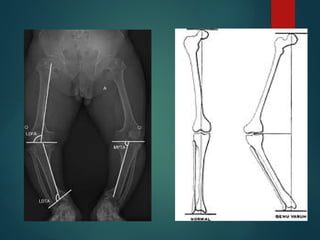

Alteraciones del eje

• Desde que los niños empiezan a

caminar y hasta

aproximadamente los 2 años de

edad, las piernas suelen tener

forma de paréntesis o

arqueadas, fenómeno

llamado genu varo.

• A partir de los 3 años, las piernas

acostumbran a adoptar una

forma de x, conocido con el

nombre de genu valgo. Se

mantiene habitualmente hasta

los 7 o 8 años, edad en que las

piernas vuelven a su posición

normal.

• Por ello, a partir de los ocho

años cualquier posición en varo

o en valgo es anormal.

RN -> Varo fisiológico: 10-15°

18 meses-> neutralización de angulación

2-3 años -> valgo fisiológico: 15°

A partir de los 8 años -> 7-8° normal

Genu Varo

 Desviación interna de la rodilla, en la

cual la porción de la extremidad distal a

la rodilla se desvía hacia la línea media

 Rodillas arqueadas (“De vaquero”)